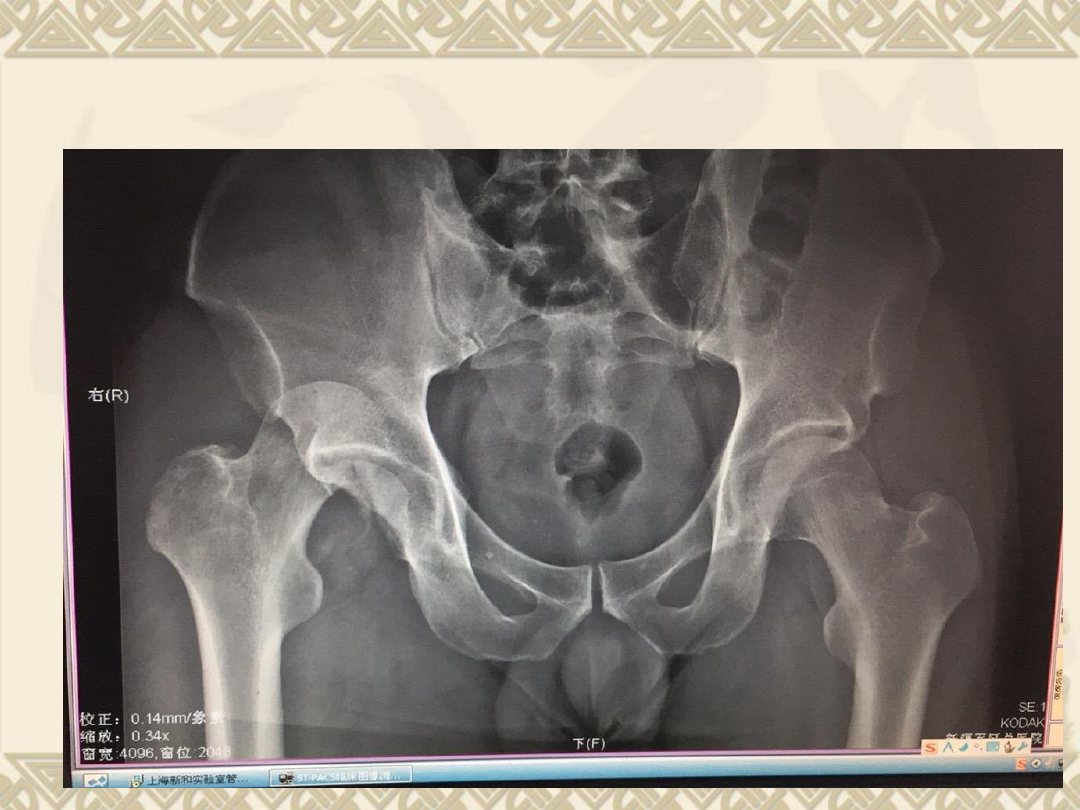

入院后拍片

v

1

、右股骨头骨折(

Pipkin

Ⅳ型骨折)

2

、髋关节后脱位

3

、髋臼后缘骨折